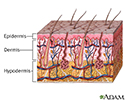

Sweating is the release of liquid from the body's sweat glands. This liquid contains salt. This process is also called perspiration.

Sweating helps your body stay cool. Sweat is commonly found under the arms, on the feet, and on the palms of the hands.

The amount you sweat depends on how many sweat glands you have.

A person is born with about 2 to 4 million sweat glands, which begin to become fully active during puberty. Men's sweat glands tend to be more active.

Sweating is controlled by the autonomic nervous system. This is the part of the nervous system that is not under your control. Sweating is the body's natural way of regulating temperature.